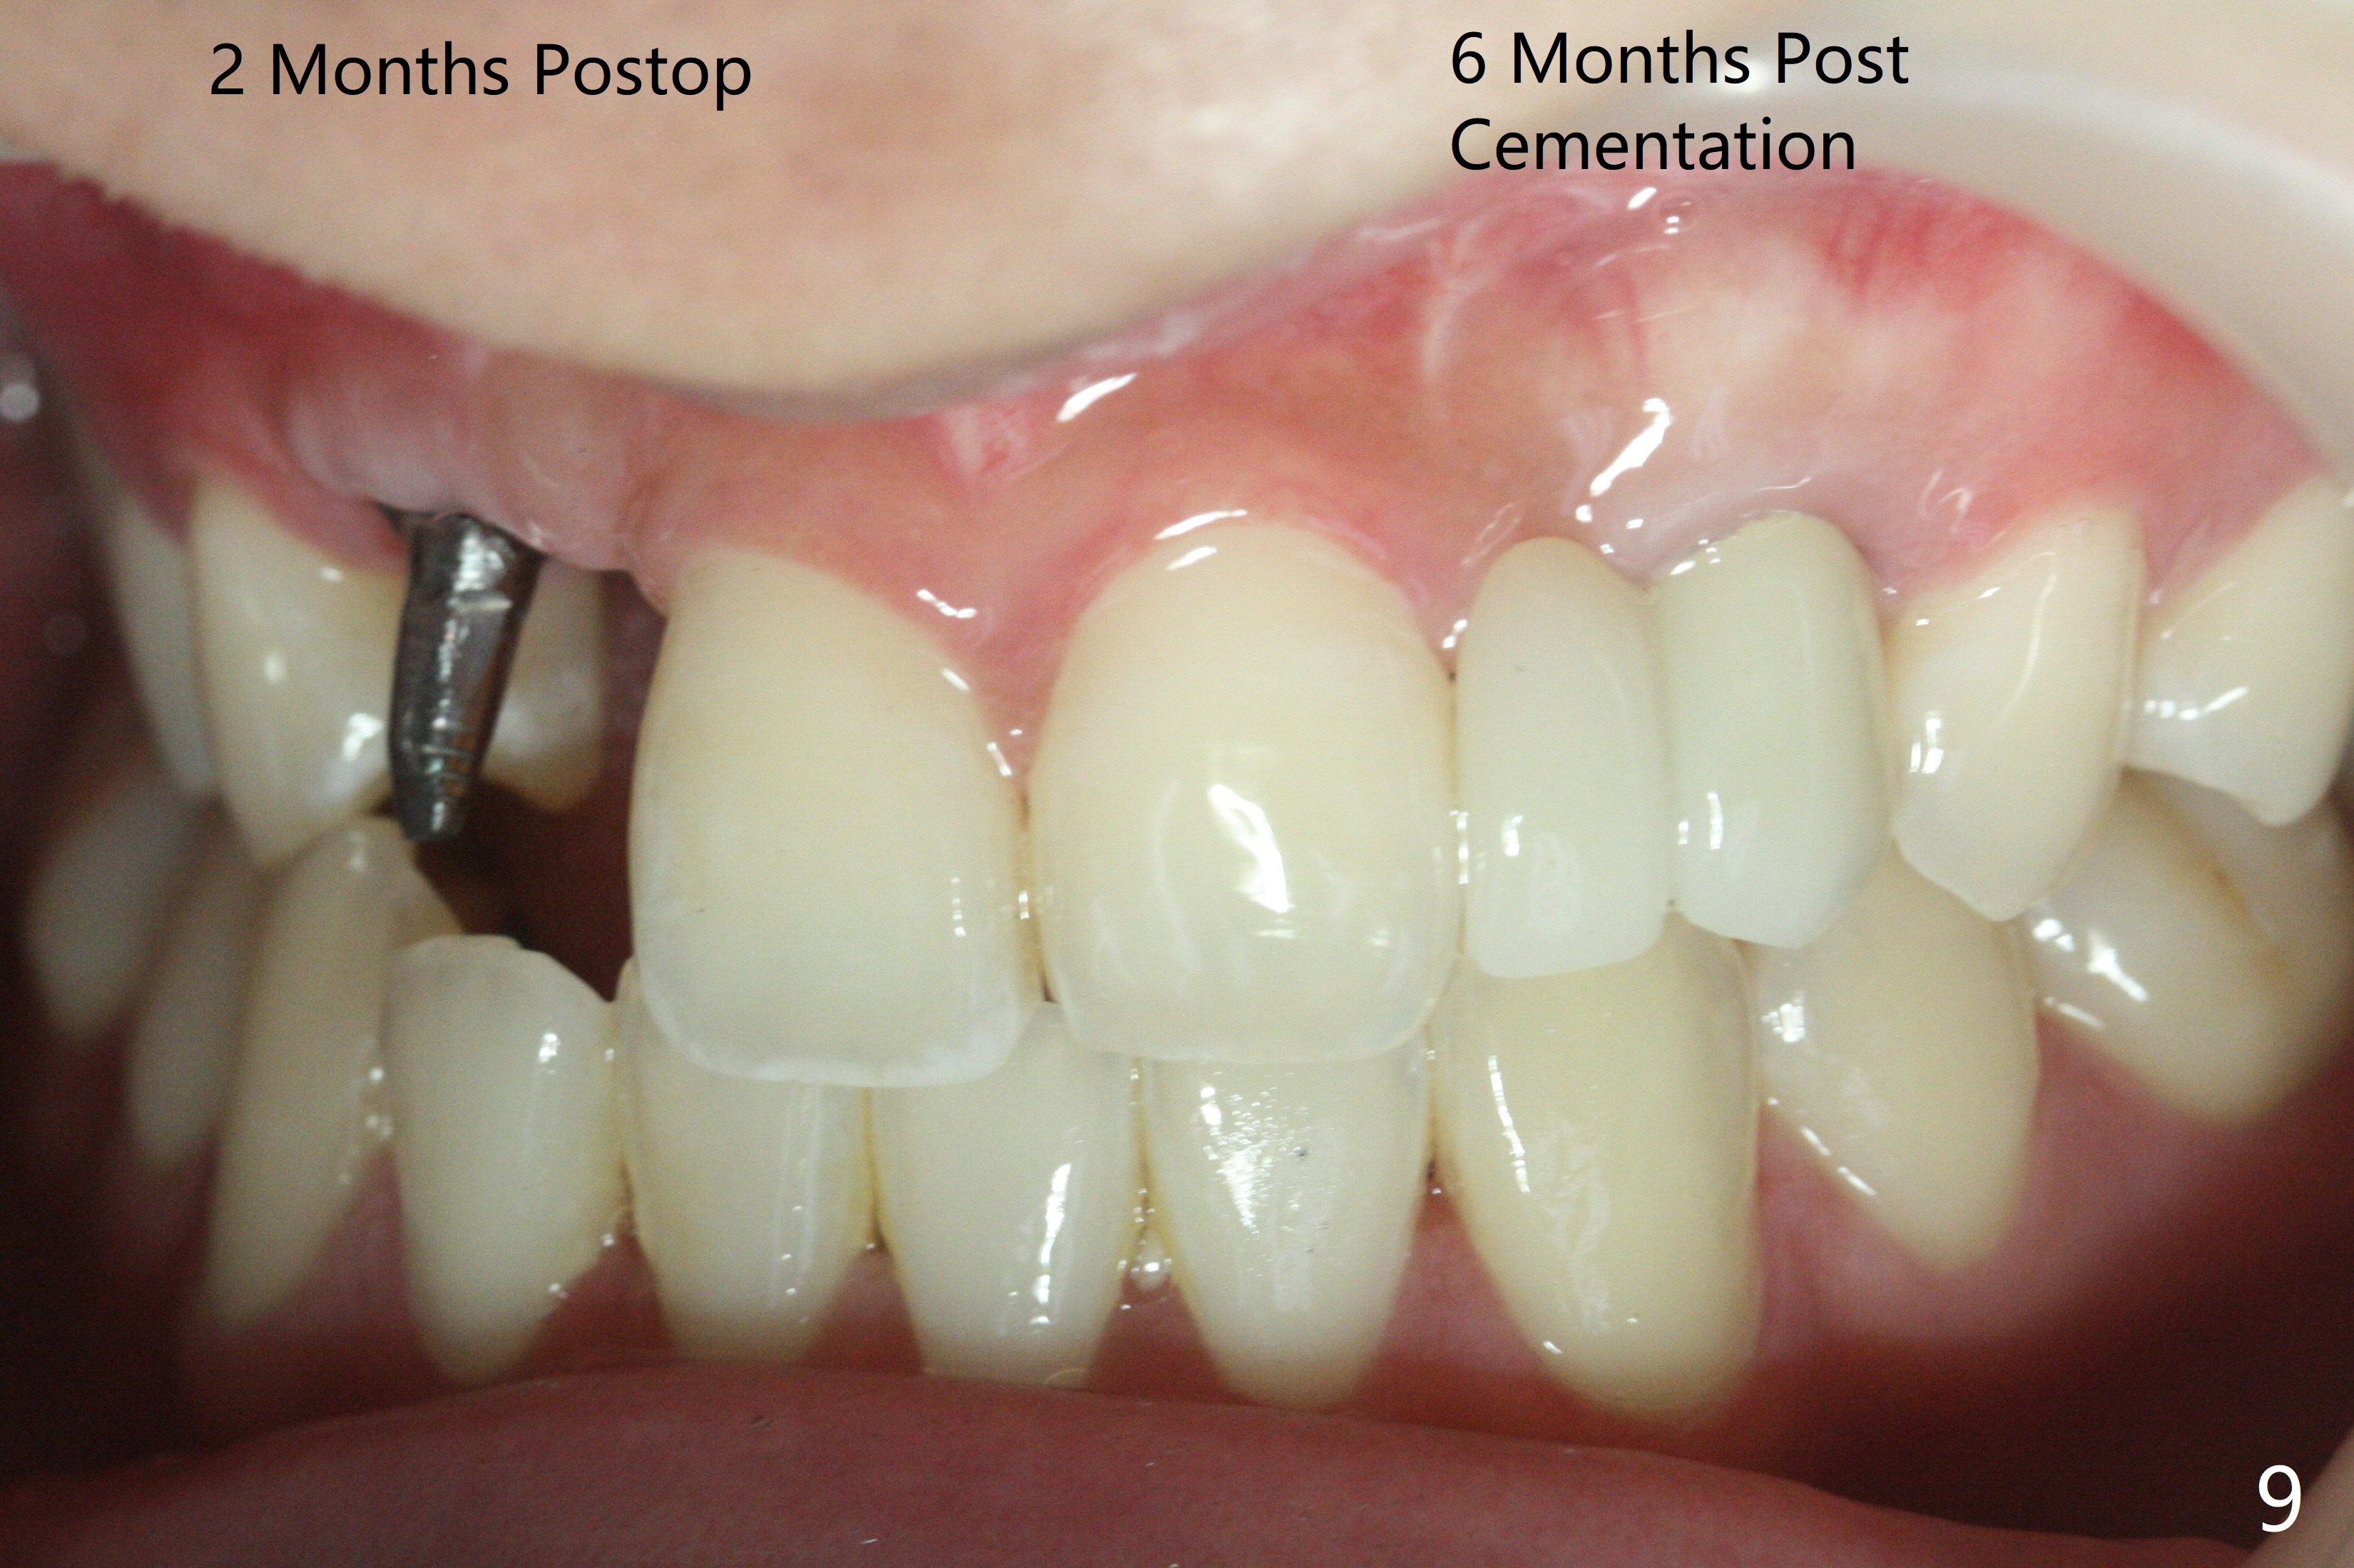

右上尖牙植体拔除,植骨后6个月,切开显示不可吸收膜覆盖的牙槽骨尚饱满(图一),不可吸收膜下面形成一个膜(可能是骨膜,图二:M),在导板指导下,植入3x12(2)毫米一段式植体,颊侧(图三),腭侧(图四)骨下,稍微穿过窦底(图五),植体覆盖粘性骨粉(图六)和PRF膜后,4-0 PGA缝合。伤口有一定张力,使用牙周敷料。术后10天没有疼痛(就没有骨坏死),由于基台存在,牙周敷料没有脱落迹象(图七),也没有撤除。敷料术后13天脱落,伤口好像正常愈合(图八)。由于病人即将回外州上学,提前取模。他喜欢左边牙冠修复形式(牙冠覆盖牙龈),而我们想让牙冠位于牙龈舌侧(图十:T(临时牙冠))。